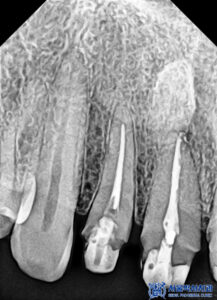

파노라마를 촬영하고

확인해 보았을 때도,

보철물이 방사선불투과성이라

치아 내부를 정밀하게

확인할 수 없었습니다.

그래서 산성동치과 서울박사치과에서는

해당 브릿지를 제거하여

내부 상황을 확인하기로

환자분과 상의 후 결정하였습니다.

제거를 하고 확인해 보니,

내부로 충치가 생긴 것을

확인할 수 있었습니다.